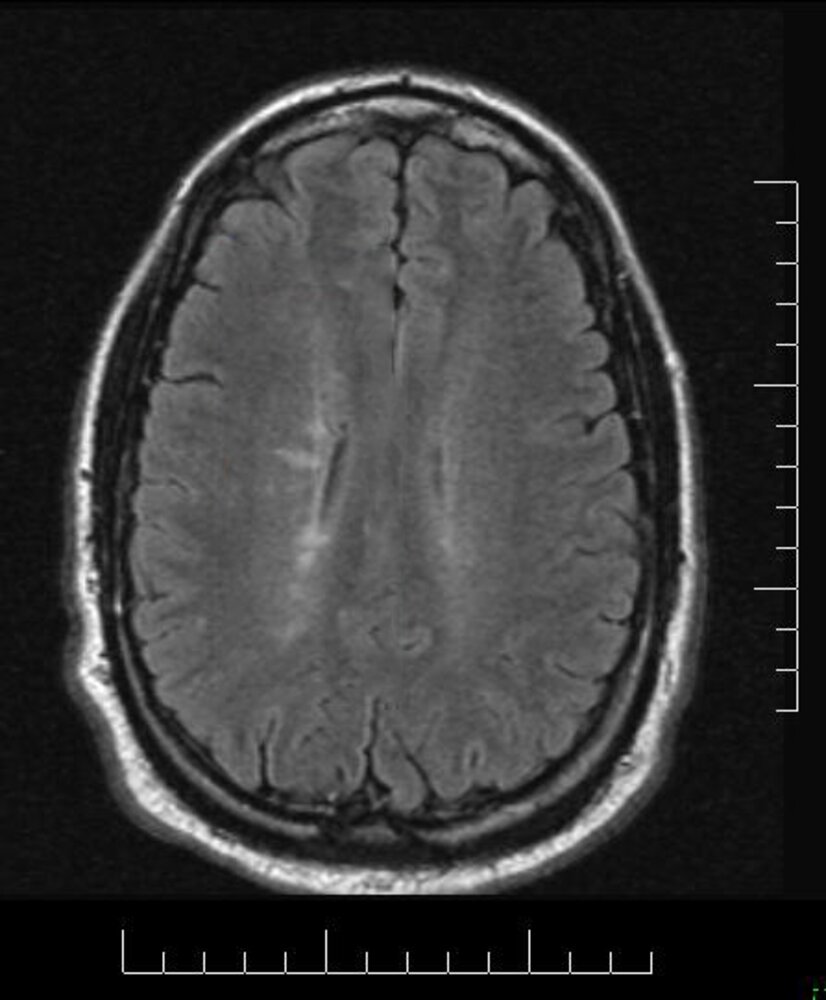

What finding on the imaging below is strongly indicative of multiple sclerosis?

Dawson Fingers